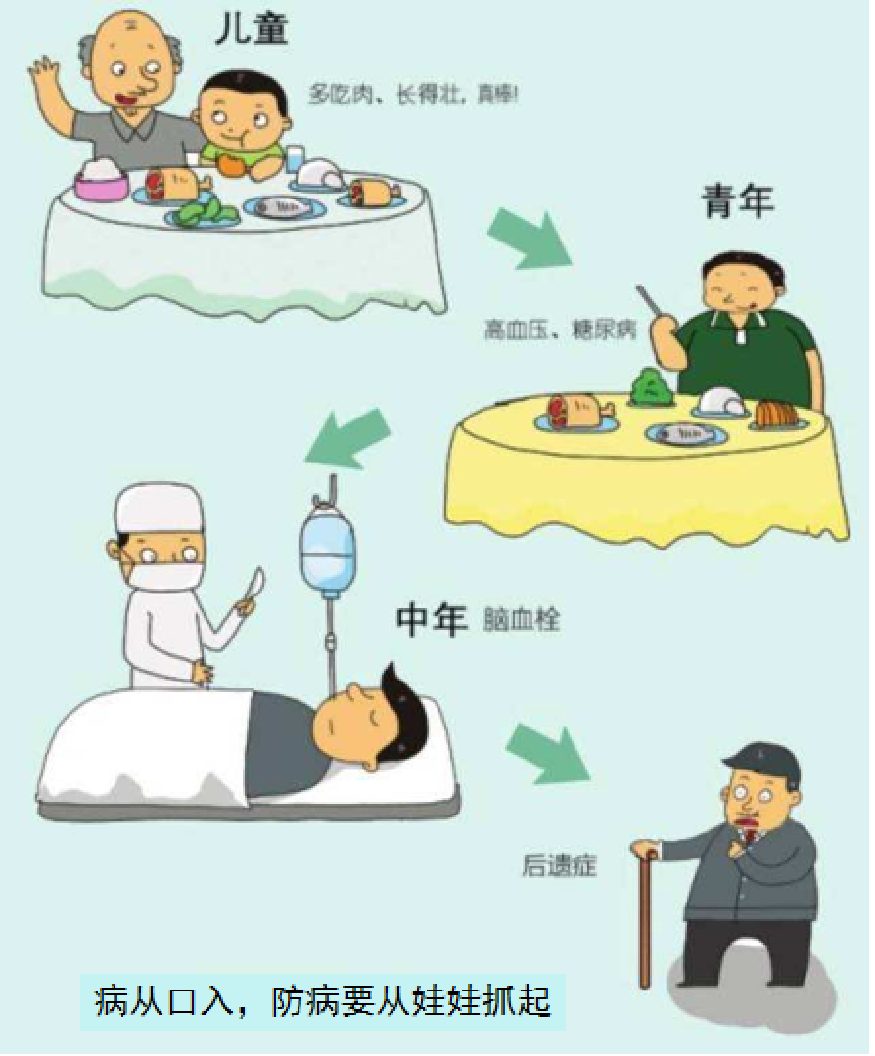

形成动脉粥样硬化的起始年龄可以非常年轻,可以从青春期的少男少女开始,甚至从孩童期就开始了。

脑梗的病程

这个才16岁的花季少女,她的同型半胱氨酸这么高(≧10μmol/L为高血同),估计她的动脉粥样硬化已经起步n年了。如果现在不开始加以控制的话,估计她在40岁左右就会出现心梗或脑梗。

人生就是这么残酷。这个病例给我们的启示是什么呢?有病要早发现,早预防,早治疗。